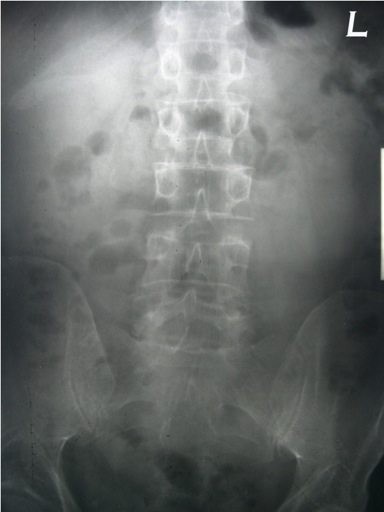

LUMBAR SPINE:

Frontal and lateral views are submitted.  Viewed coronally, there is a mild left convexity with the apex at L3.  The left femoral head and iliac crest are lower than the right by 12mm.  Viewed sagittally, the upper lumbar spine is slightly hypolordotic.

Bone density is moderately diminished, with increased lucency of all osseous structures and vertical striations in the vertebral bodies.  Mild osteophytic proliferation is seen on the vertebral bodies from L2 through L5.  Calcific plaquing is visible along the course of the abdominal aorta.

IMPRESSIONS:

1.	Atherosclerosis.

2.	Moderate osteoporosis.  Follow up is recommended.

3.	Mild spondylosis, L2 through L5.

4.	Apparent 12mm short left leg.  Clinical correlation is recommended.

5.	Postural alterations as described above.